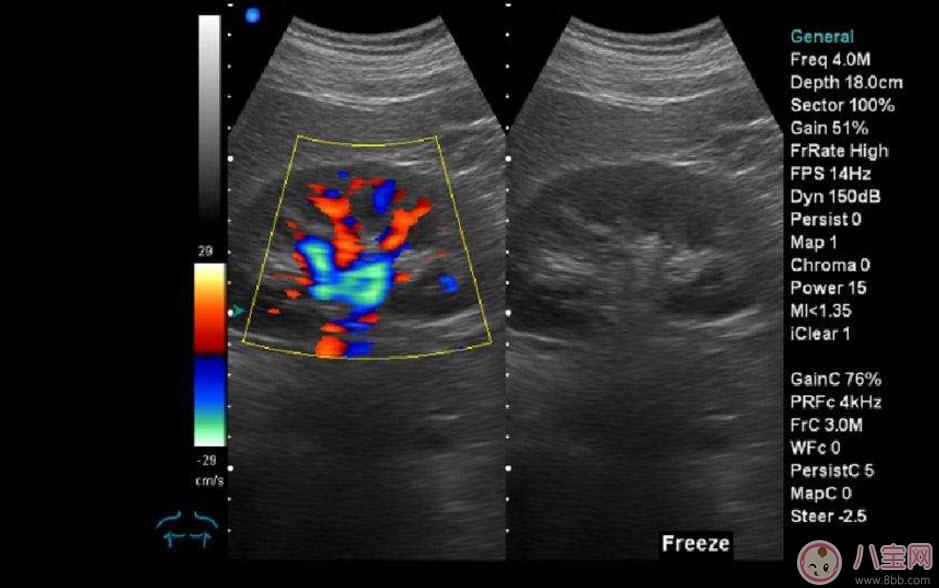

b超和彩超的区别??B超也称为二维超声,分为黑白的和彩色的两种 。彩超其实还是黑白的,彩超简单的说就是高清晰度的黑白B超再加上彩色多普勒,既具有二维超声结构图像的优点,又提供了血流动力学的丰富信息 。彩超的分辨率会比一般黑白B超高一些,所以在需要做比较细致的检查的时候,更多的医生愿意通过彩超来检查 。例如,因为彩超能用彩色标注血流,所以当脐带绕颈的时候就会看见宝宝的脖子上呈U形或者W形的血流,对是否脐带绕颈也就一目了然了 。目前用于产检的超声波一般都是二维的 。

什么是普通的彩超除了能观察到通过B超观察到的一切外,彩超能够直观成像,显示更清晰,结果也更快速,可发现异常血流,为诊断胎儿先天性心脏缺陷提供了诊断依据 。价格要比B超贵,大概在150元左右(会根据各地具体情况的不同而上下浮动) 。二维彩超适用于整个孕期,特别是临产前 。二维彩超的图像也并非就是彩色的,而是用彩色标注心脏、血流等指标,其实就是高清晰度的黑白B超再加上彩色多普勒 。观测到的图像以红蓝两色血流方向为主,面向探头的呈现红色,反之为蓝色 。这种技术能够观测到胎儿的血液流动情况,有利于及时发现胎儿的异常 。比如,发现胎儿颈部有血流环,则意味着发生了可导致窒息死亡的脐带绕颈 。